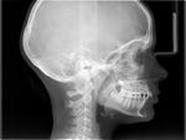

Nella notte dell'8 novembre 1895 Wilhelm Conrad Röentgen Professore di

Fisica Sperimentale all'Università di Würzburg in Baviera scopri dei "raggi"

di origine sconosciuta che per tale ragione chiamo X (la lettera X e utilizzata

per indicare le grandezze incognite in fisica).

L'attraversamento dei tessuti da parte di queste radiazioni permette di impressionare speciali pellicole in grado di rendere una volta sviluppate e fissate il "plastico" del corpo attraversato. La prima radiografia che è apparsa al mondo scientifico è stata quella della mana della Sig.ra Röentgen.

La pellicola radiografica

rappresenta di fatto una mappa delle densità attraversate dal fascio di

radiazioni ed è per questo motivo che le ossa appaiono chiare in quanto

assorbono quasi tutte le radiazioni mentre il polmone appare scuro perche la

maggior parte delle radiazioni raggiungono la pellicola impressionandola.